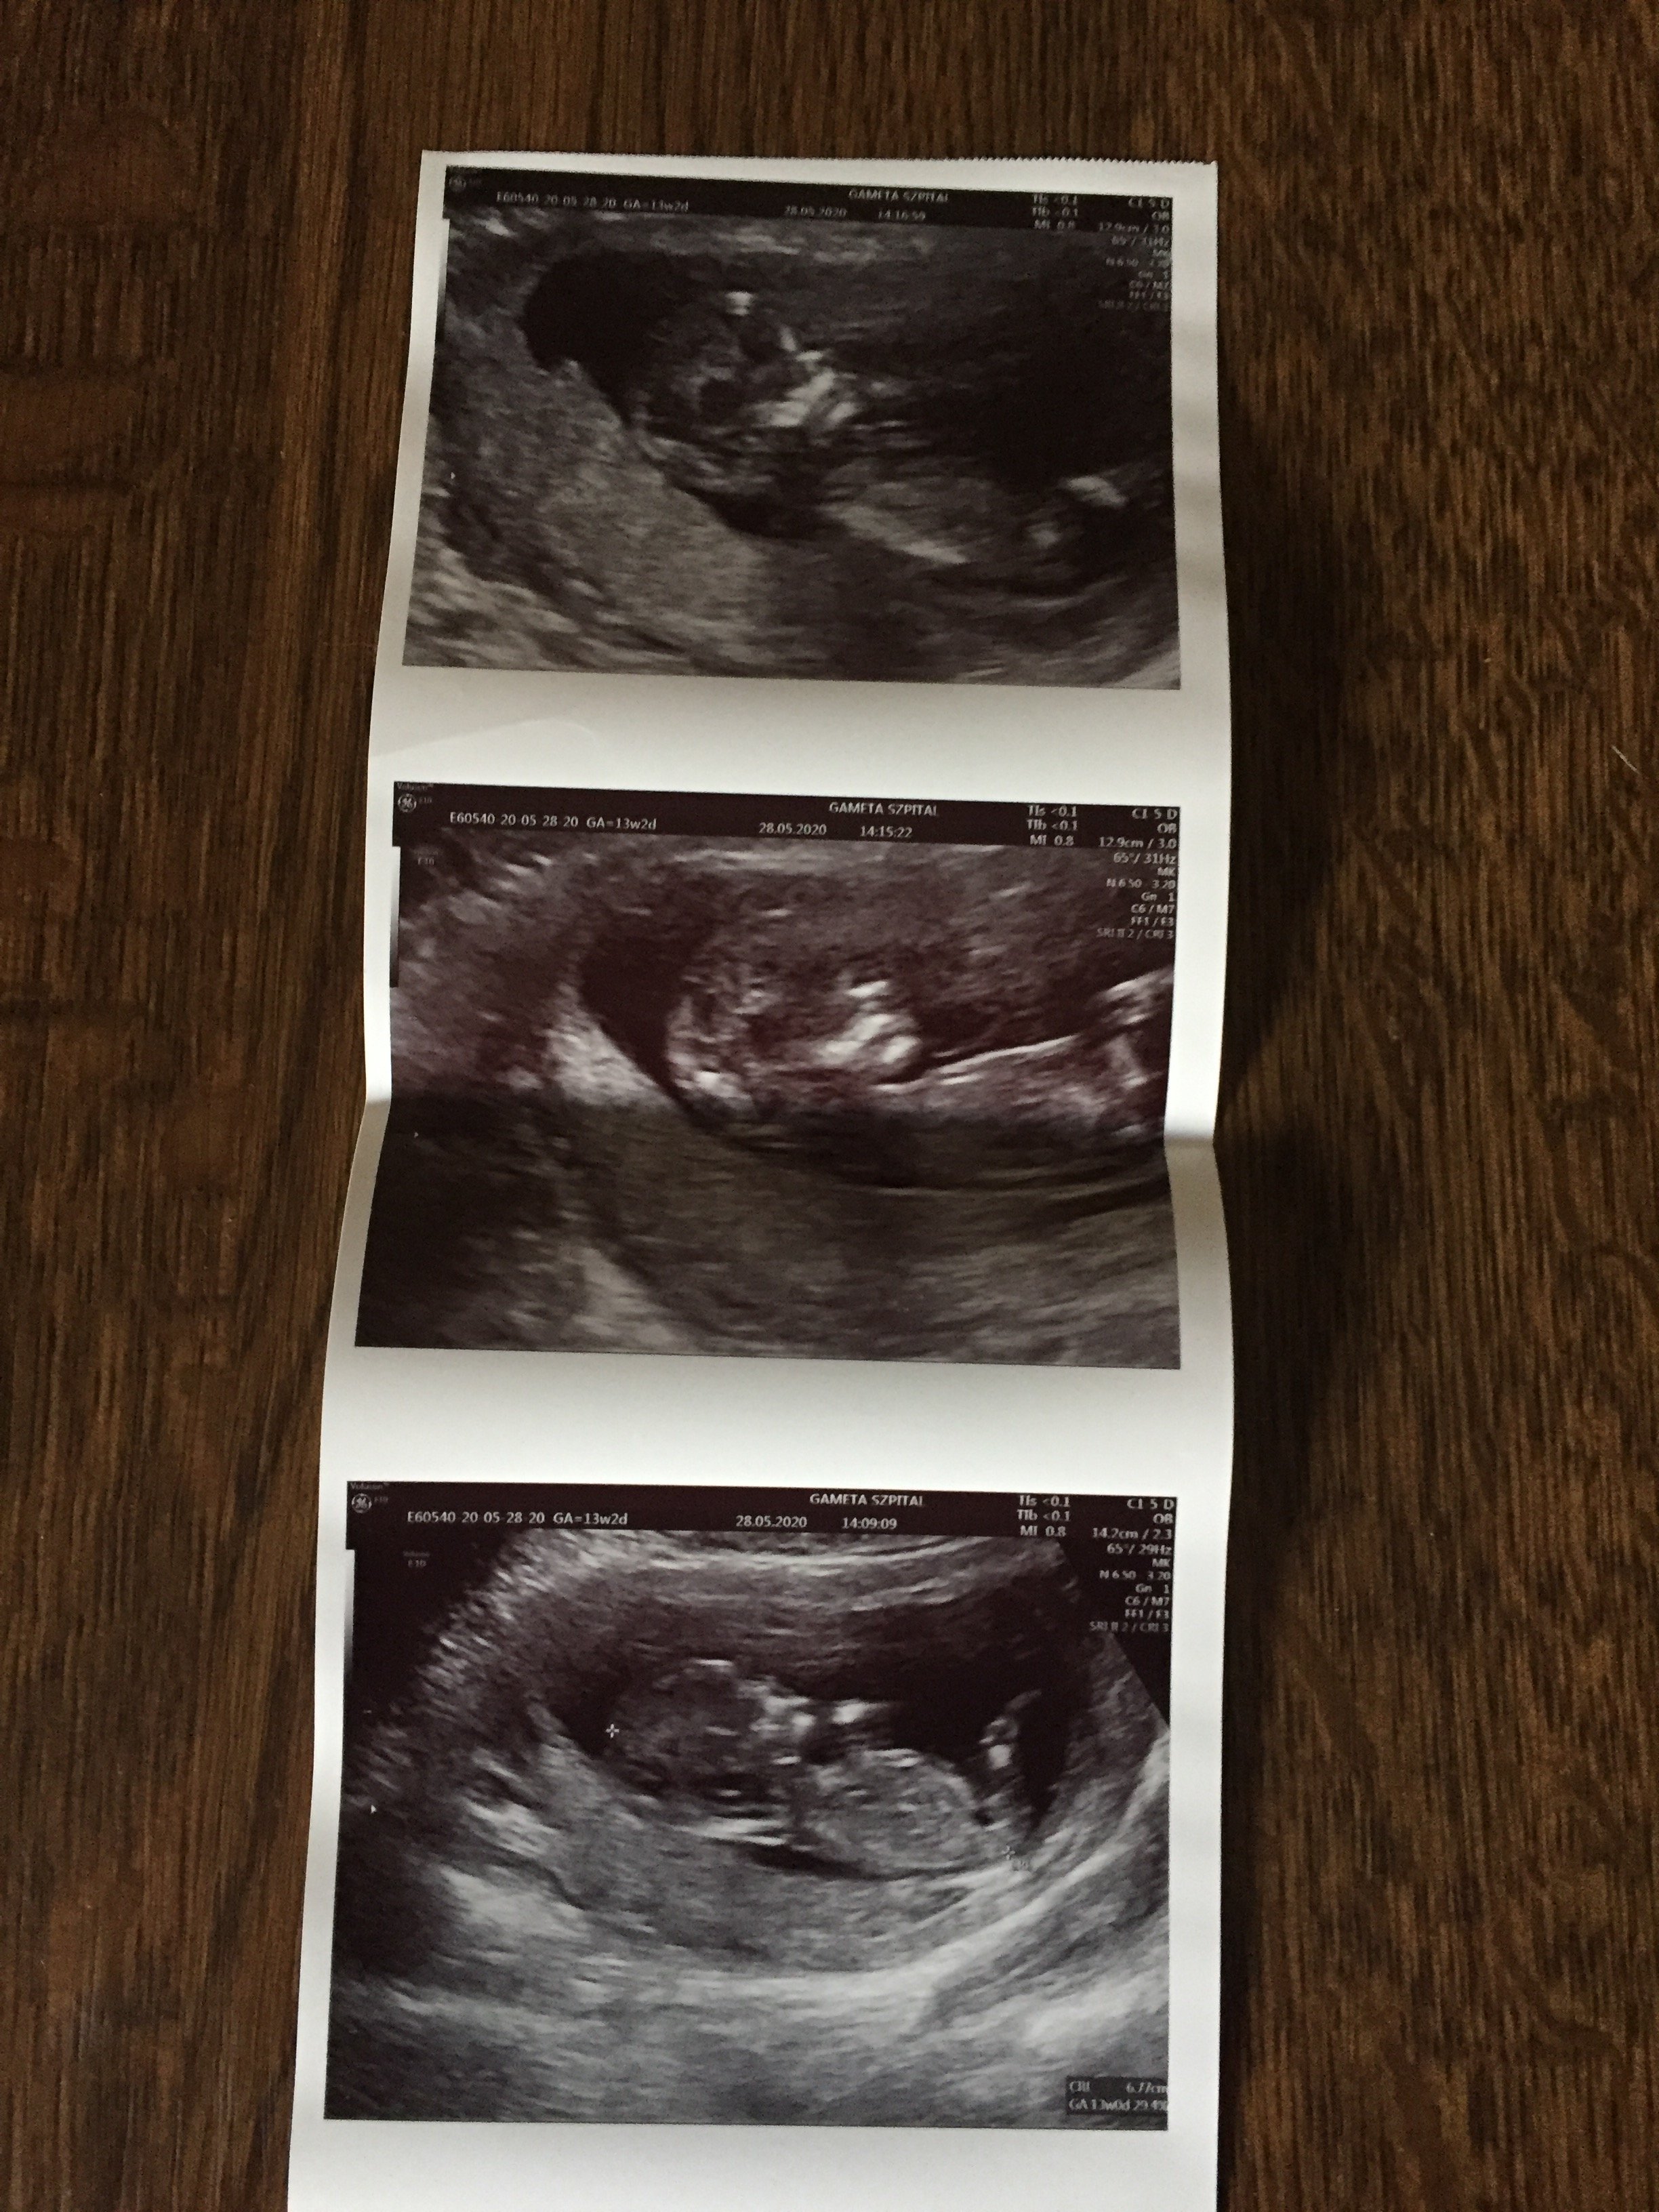

Pięknie, serdeczne gratulacjeNo i ja się w końcu pochwale moja kruszynka ❤ Mamy prawie 7 cm (6,8) dziś 13 równy tydzień wiec jutro wkraczamy w 14 wowwszystko prawidłowo na usg prenatalnym żadnych uwag zdrowa dzidzia. Najważniejsze, ze krwiak się całkowicie wchłonął juuupi nie ma po nim śladu

mąż nie mógł wejść ze mną niestety ale całe usg dostałam na pendrivie wiec widzieli już rodzice no i mąż również cudowny filmik jak wszystko mierzył lekarz i jak cudownie podskakiwała i kopała bo.... prawdodpobnie dziewczynka